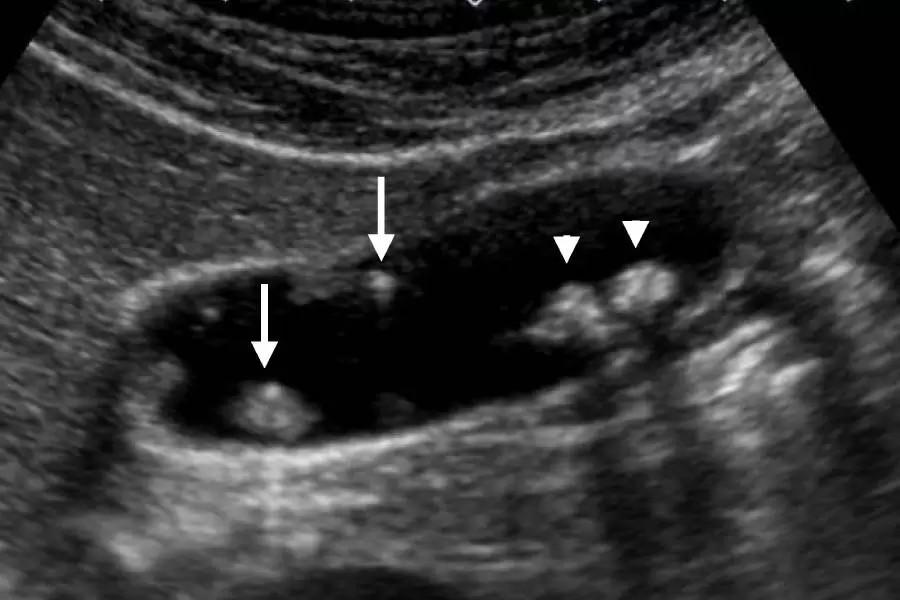

• Ultrasound: This imaging test uses sound waves to produce images of the gallbladder and can catch the presence of polyps.